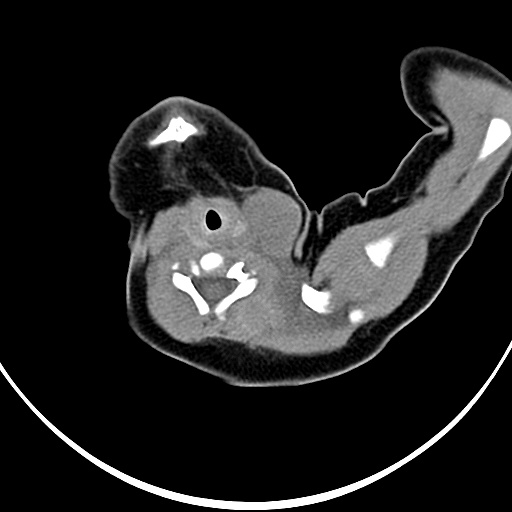

考虑淋巴水瘤。

淋巴管囊肿可能性大

病灶与左侧胸锁乳突肌分界不清,软组织密度,不似囊性改变,从病人的年龄及病变性状首先要除外先天性斜颈(肌性斜颈)可能。

左侧胸锁乳突肌肿大,考虑产伤所致

胸锁乳突肌挛缩(斜颈)?